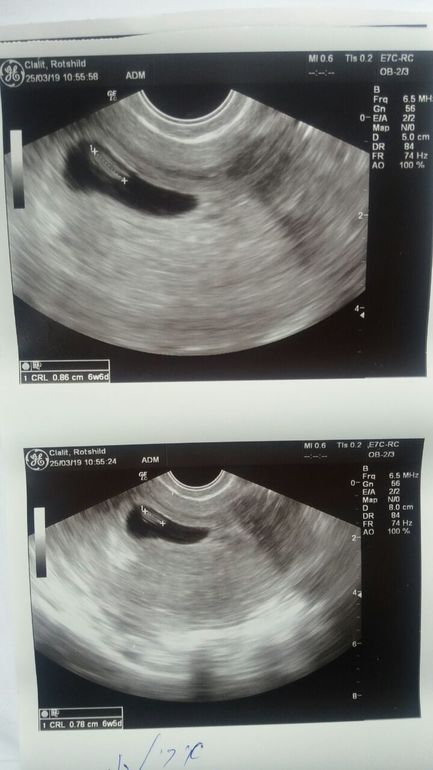

Вобщем вот:

Размер эмбриона 8.6 мм-написано соответствует 6,6 недель. Сегодня как раз от первого узи , где определилось как 5.2-5.3 ровно 7 недель. Хотя врач сказала что в компе там другие параметры и она насчитала отставание. Но я сравниваю сканы и отставания не вижу. 13,03 узи определял как 5 и 2 . Сегодня 25,03 и 6и6...Не знаю о какой задержке она говорит. Сказала прийти через неделю..тут я уже взвыла, говорю хочу через 2, не раньше.

И врача поменять! ААА и самое главное же не написала-ЕСТЬ СЕРДЦЕБИЕНИЕ!